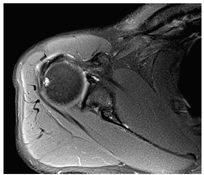

所有患者术中均未发生臂丛牵拉或灌洗液外渗造成颈胸背筋膜腔水肿等并发症。随访期间无关节感染或其他并发症出现。术后6个月时肌电图未见神经损伤,MRI未见囊肿复发(图5)。所有患者均重返伤前工作岗位,对治疗结果满意。